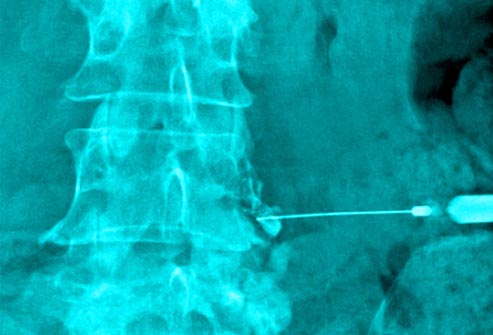

Injections

If simpler therapies and medications aren’t helping, your doctor may recommend injections to the back. One procedure, called a nerve root block, targets irritated nerves. Injections for back pain usually contain steroid medication.